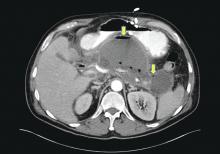

Pancreatic necrosis with acute necrotic collection: arrowhead indicates viable enhancing pancreas; arrows indicate nonenhancing ischemic tissue.